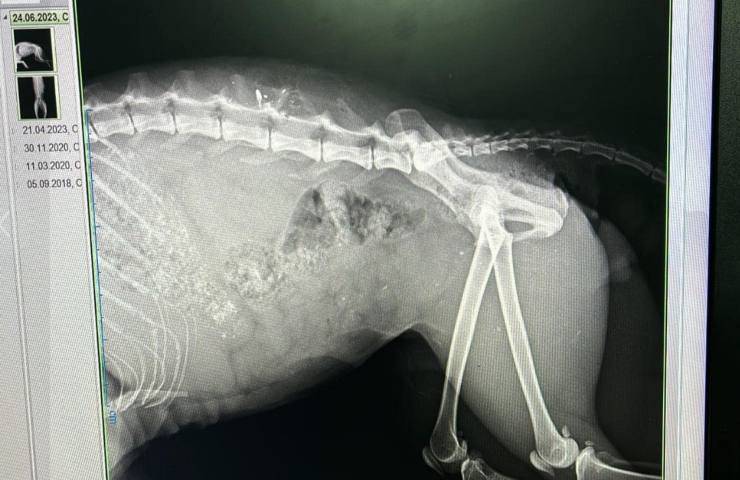

Il proiettile ha scalfito la colonna, il gatto è gravissimo

Il dolcissimo Gastone è ricoverato presso la clinica veterinaria Costa d’Argento di Albinia e sta lottando coraggiosamente per la sua vita. Il proiettile ha danneggiato la sua colonna vertebrale e attualmente ancora non è chiaro ne se il povero felino sarà più in grado di utilizzare gli arti inferiori ne se il proiettile abbia danneggiato organi interni che potrebbero compromettere la sua capacità di svolgere adeguatamente le funzioni vitali. Gastone è anche febbricitante. La febbre dovuta sicuramente ad un infezione ha fatto si che l’intervento chirurgico fosse ritardato, anche se c’è una piccola speranza che le cure mediche possano almeno mitigare parte del danno.